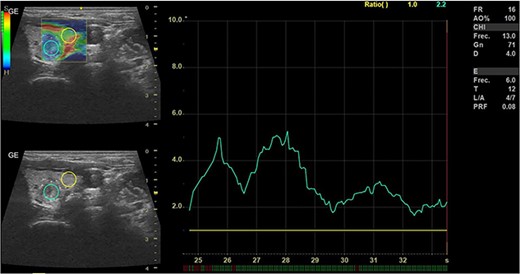

In May 2022, a thyroid ultrasound revealed a solid isoechoic left lobe TN measuring 12 × 11 × 13 mm, characterized by microcalcifications and irregular borders (Fig. 1). The color-flow Doppler ultrasound indicated increased perfusion, leading to its classification as a TI-RADS 5 nodule (Fig. 2). Elastography yielded a value of 2.2 (Fig. 3). Fine-needle aspiration confirmed Bethesda VI, consistent with thyroid papillary carcinoma.

Doppler thyroid ultrasound: transversal view, left lobe nodule doppler. Pre-RFA procedure.

Thyroid ultrasound: elastography, Left lobe and nodule. Pre-RFA procedure.